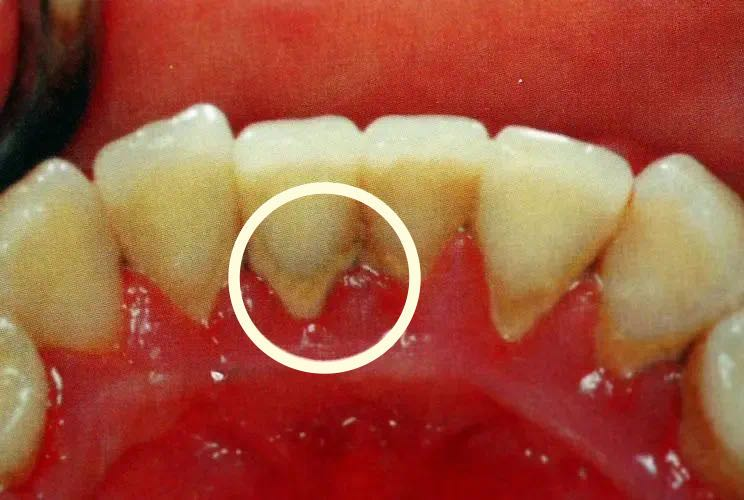

一旦出现牙龈萎缩,表现为:牙龈红肿,刷牙出血;牙齿变长,牙缝变大;牙根开始暴露;遇到冷热酸甜,牙齿敏感;牙齿松动。

温馨提醒:牙龈萎缩是导致牙齿缺失的重要原因,所以患有牙周病的朋友要注意控制病情发展,防止牙龈继续萎缩,避免牙齿松动甚至脱落。